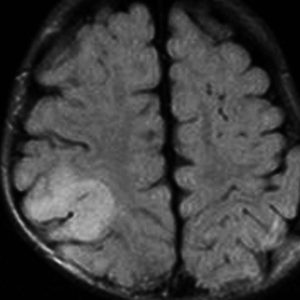

2歳時に偶然発見された,大脳皮質の限局性異形成です。10歳まで症状はでていません。

右側頭葉中側頭回の皮質が厚くなっています。T1強調画像では等信号で見づらいですが,下のフレア画像とT2強調画像では高信号になるのでわかります。

低悪性度グリオーマと間違われることがありますが,大脳皮質だけが異常な信号になっていて,皮質下白質に異常所見がないことが鑑別点です。